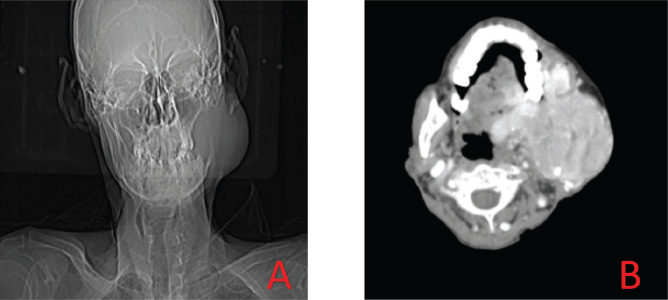

摘要肾细胞癌(RCC)转移至头颈部是罕见的。肾细胞癌转移灶具有放射抵抗性,手术是主要的治疗方式。在这里,我们提出一个73岁男性的病例,他表现为左面部肿胀,活检和免疫组织化学显示转移性肾细胞癌。再次对患者进行复查,确定了左肾原发病变。

Metastasis of renal cell carcinoma (RCC) to the head and neck region is rare. The metastases of RCC are radioresistant with surgery as the primary treatment modality. Here, we present a case of a 73-year-old male who presented with left facial swelling which on biopsy and immunohistochemistry showed metastatic RCC. The patient was re-evaluated again and the left renal primary was found out.